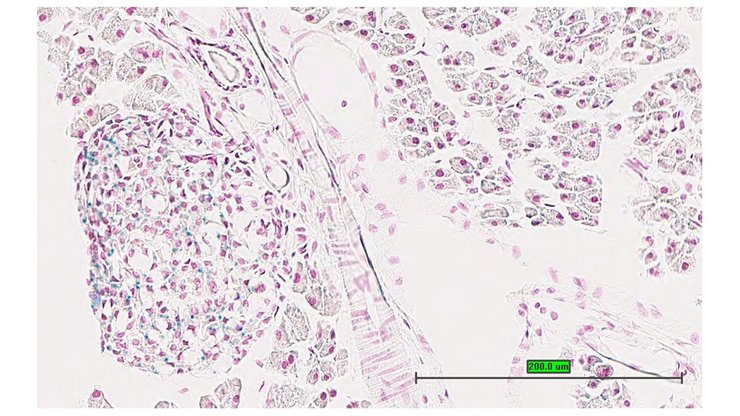

TS28: pancreas Present UC Davis_1870104

Specimen UC Davis_1870105: postnatal adult; Atf6btm1.1(KOMP)Vlcg/Atf6b+ (more )

Structure Level Pattern Image Note

TS28: pancreas Present UC Davis_1870105

TS28: pancreas Present UC Davis_1870161

Specimen UC Davis_1870162: postnatal adult; Atf6btm1.1(KOMP)Vlcg/Atf6b+ (more )

TS28: pancreas Present UC Davis_1870162

Specimen UC Davis_1870163: postnatal adult; Atf6btm1.1(KOMP)Vlcg/Atf6b+ (more )

TS28: pancreas Present UC Davis_1870163